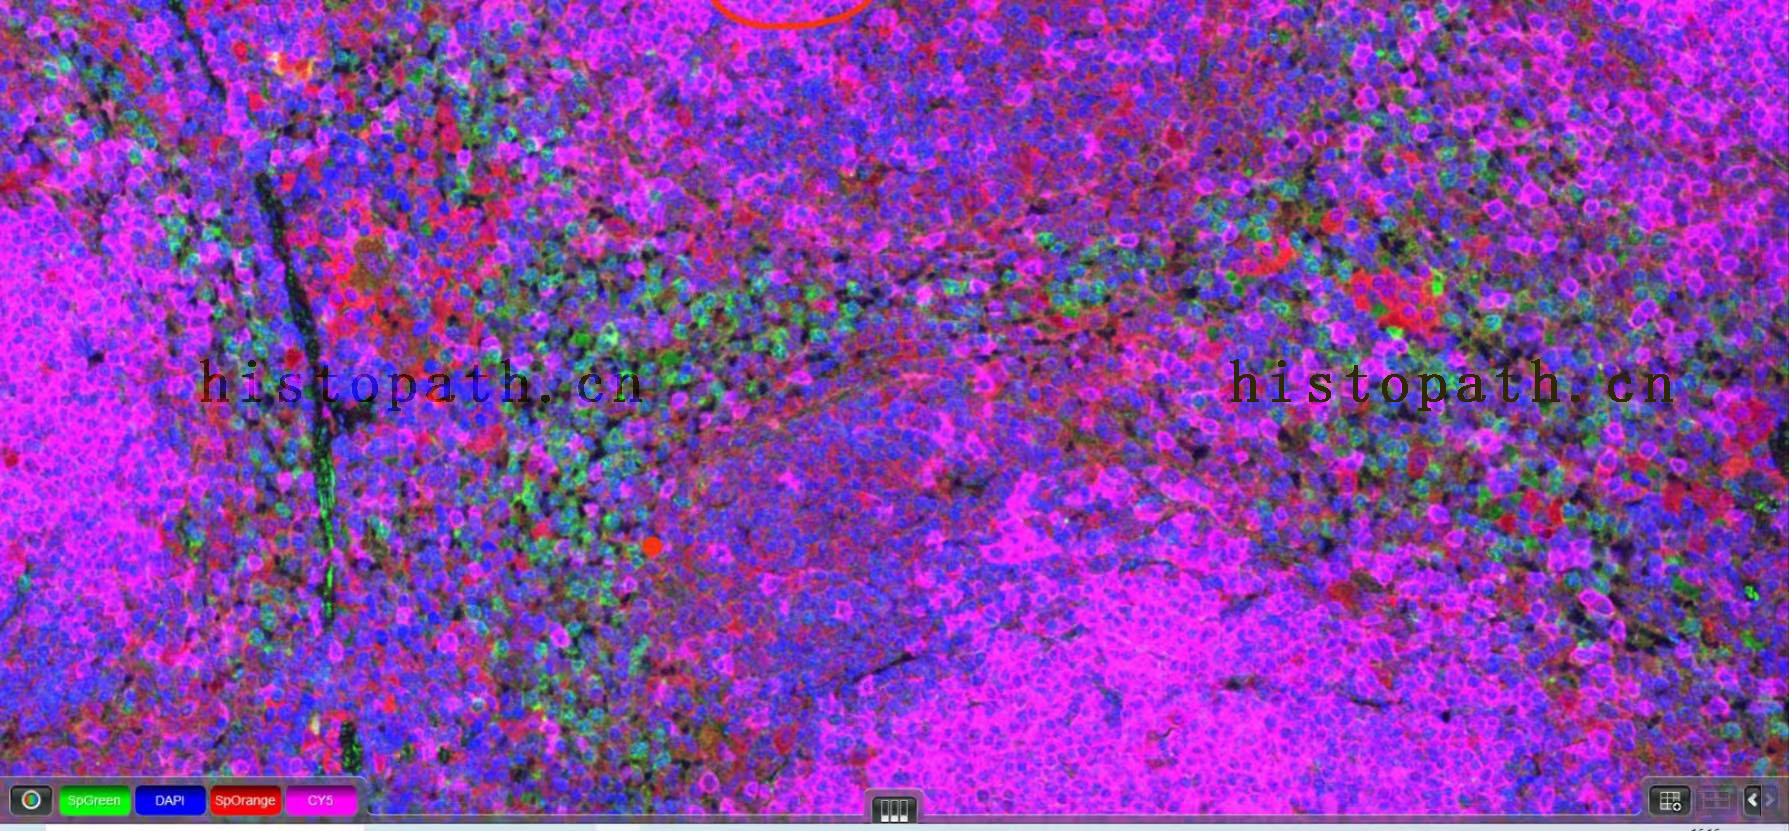

10、镜检拍照:切片置于扫描仪下采集图像或荧光显微镜下拍照。(DAPI紫外激发波长330-380nm,发射波长420nm,发蓝光;FITC激发波长465-495nm,发射波长515-555 nm,发绿光;CY3激发波长510-560,发射波长590nm,发红光. CY5激发波长 608-648nm, 发射波长672-712。 DAPI染出来的细胞核在紫外的激发下为蓝色,阳性表达为相应荧光素标记的红光,绿光

10、镜检拍照:切片置于扫描仪下采集图像。(DAPI紫外激发波长330-380nm,发射波长420nm,发蓝光;FITC激发波长465-495nm,发射波长515-555 nm,发绿光;CY3激发波长510-560,发射波长590nm,发红光. CY5激发波长 608-648nm, 发射波长672-712。 DAPI染出来的细胞核在紫外的激发下为蓝色,阳性表达为相应荧光素标记的红光,绿光 。